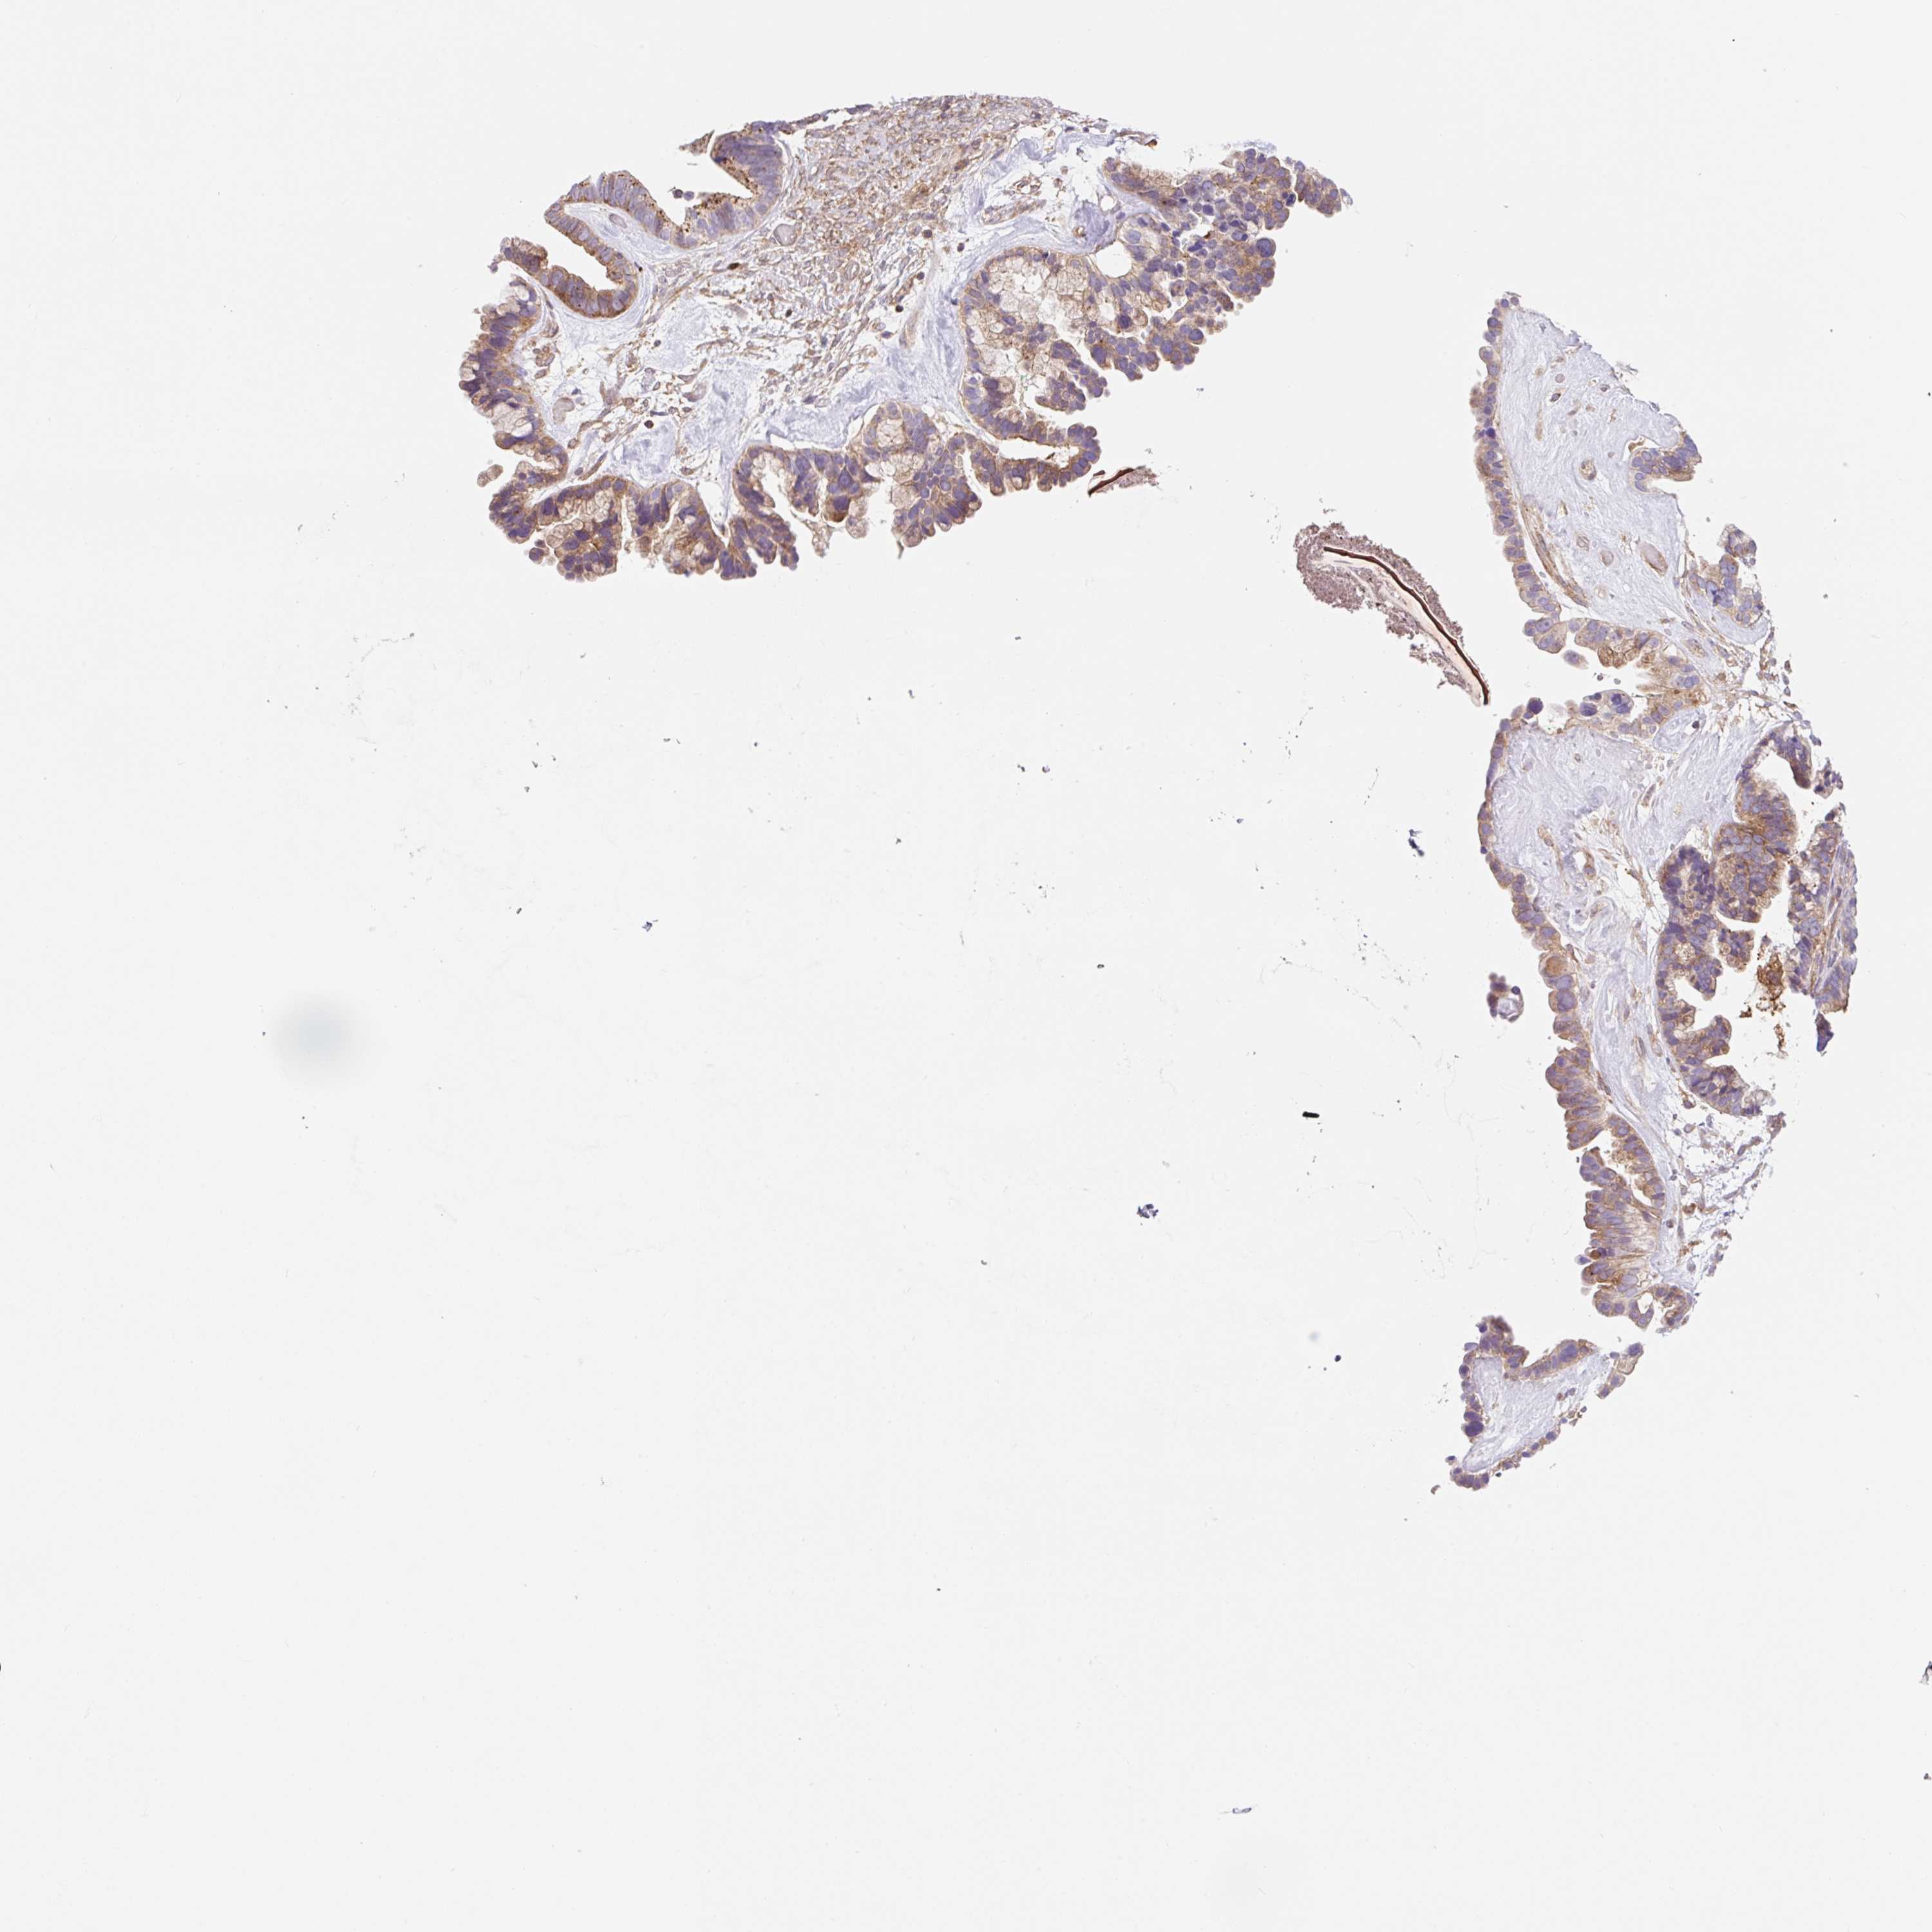

OVARIAN CANCER - Protein expressioni

A mouse-over function shows sample information and annotation data. Click on an image to view it in a full screen mode. Samples can be filtered based on level of antibody staining by selecting one or several of the following categories: high, medium, low and not detected. The assay and annotation is described here.

Note that samples used for immunohistochemistry by the Human Protein Atlas do not correspond to samples in the TCGA dataset.

Antibody stainingi

Antibody staining in the annotated cell types in the current human tissue is reported as not detected, low, medium, or high, based on conventional immunohistochemistry profiling in selected tissues. This score is based on the combination of the staining intensity and fraction of stained cells.

Each image is clickable and will lead to virtual microscopy that enables deeper exploration of all samples and also displays staining intensity scores, fraction scores and subcellular localization as well as patient and tissue information for each sample.

Antibody CAB018751

Antibody CAB034411

Staining

Cystadenocarcinoma, serous, NOS

Carcinoma, endometroid

Cystadenocarcinoma, mucinous, NOS

Carcinoma, NOS